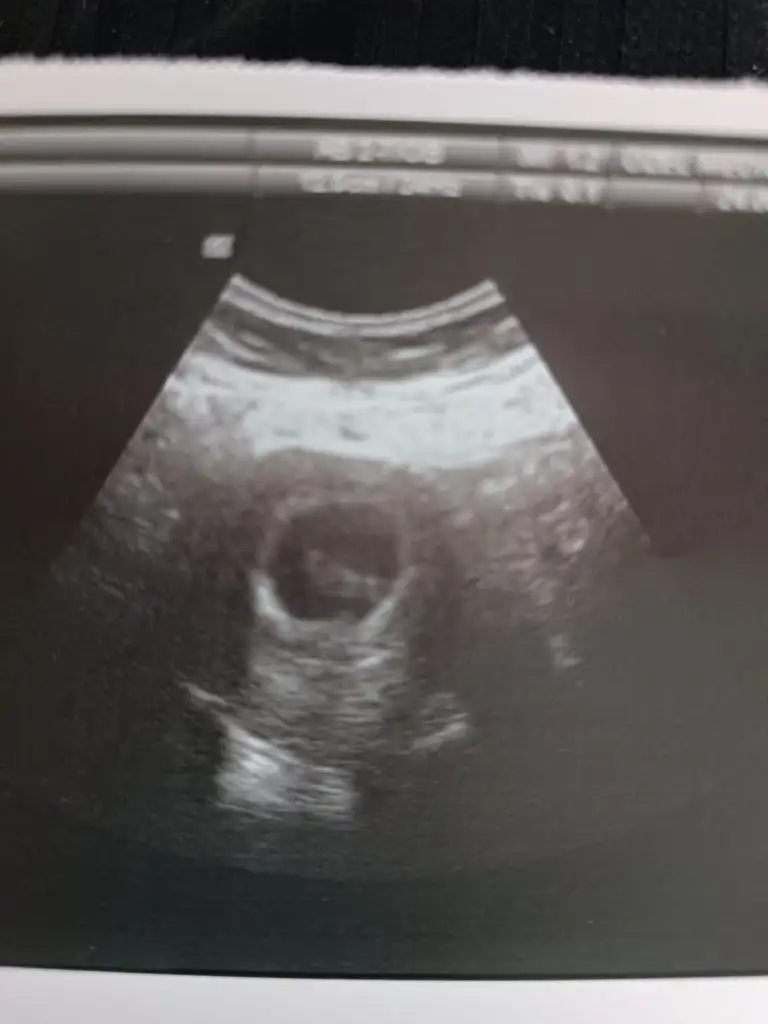

Çok şükür bebek büyümüş her şey yolunda iki hafta sonra kontrole gideceğiz hareket ettiğini bile gördüm

Yok mu ultrason kağıdı ya bende aşırı merak ediyorum heyecanlandimÇok şükür bebek büyümüş her şey yolunda iki hafta sonra kontrole gideceğiz hareket ettiğini bile gördüm

Tüp bebekte Çin takvimi nasıl oluyor ki sonuçta dondurulmuş embriyo transferi olan da varKızlar kese ve bebeğin fotoğrafı kızımda da böyle yusyuvarlaktı ama yüzük testinde ve çin takviminde erkek görünüyor4 hafta sonra azıcık 8 hafta sonra de net şekilde inşallah öğreniriz hayırlısı ile

Maşallah sağlıcakla kucağınıza almayı nasip etsin AllahKızlar kese ve bebeğin fotoğrafı kızımda da böyle yusyuvarlaktı ama yüzük testinde ve çin takviminde erkek görünüyor4 hafta sonra azıcık 8 hafta sonra de net şekilde inşallah öğreniriz hayırlısı ile

Kızımda öyleydi böyle şeyleri internetten okuyorum tabikide yuvarlak olup erkek olanda çoktur kesin yani ama nasip hayırlısı ile sağlıklı olsunlardaMaşallah sağlıcakla kucağınıza almayı nasip etsin Allahkese yuvarlak olunca kız mı oluyor acaba ilk defa duyuyorum da takip edeyim ben de